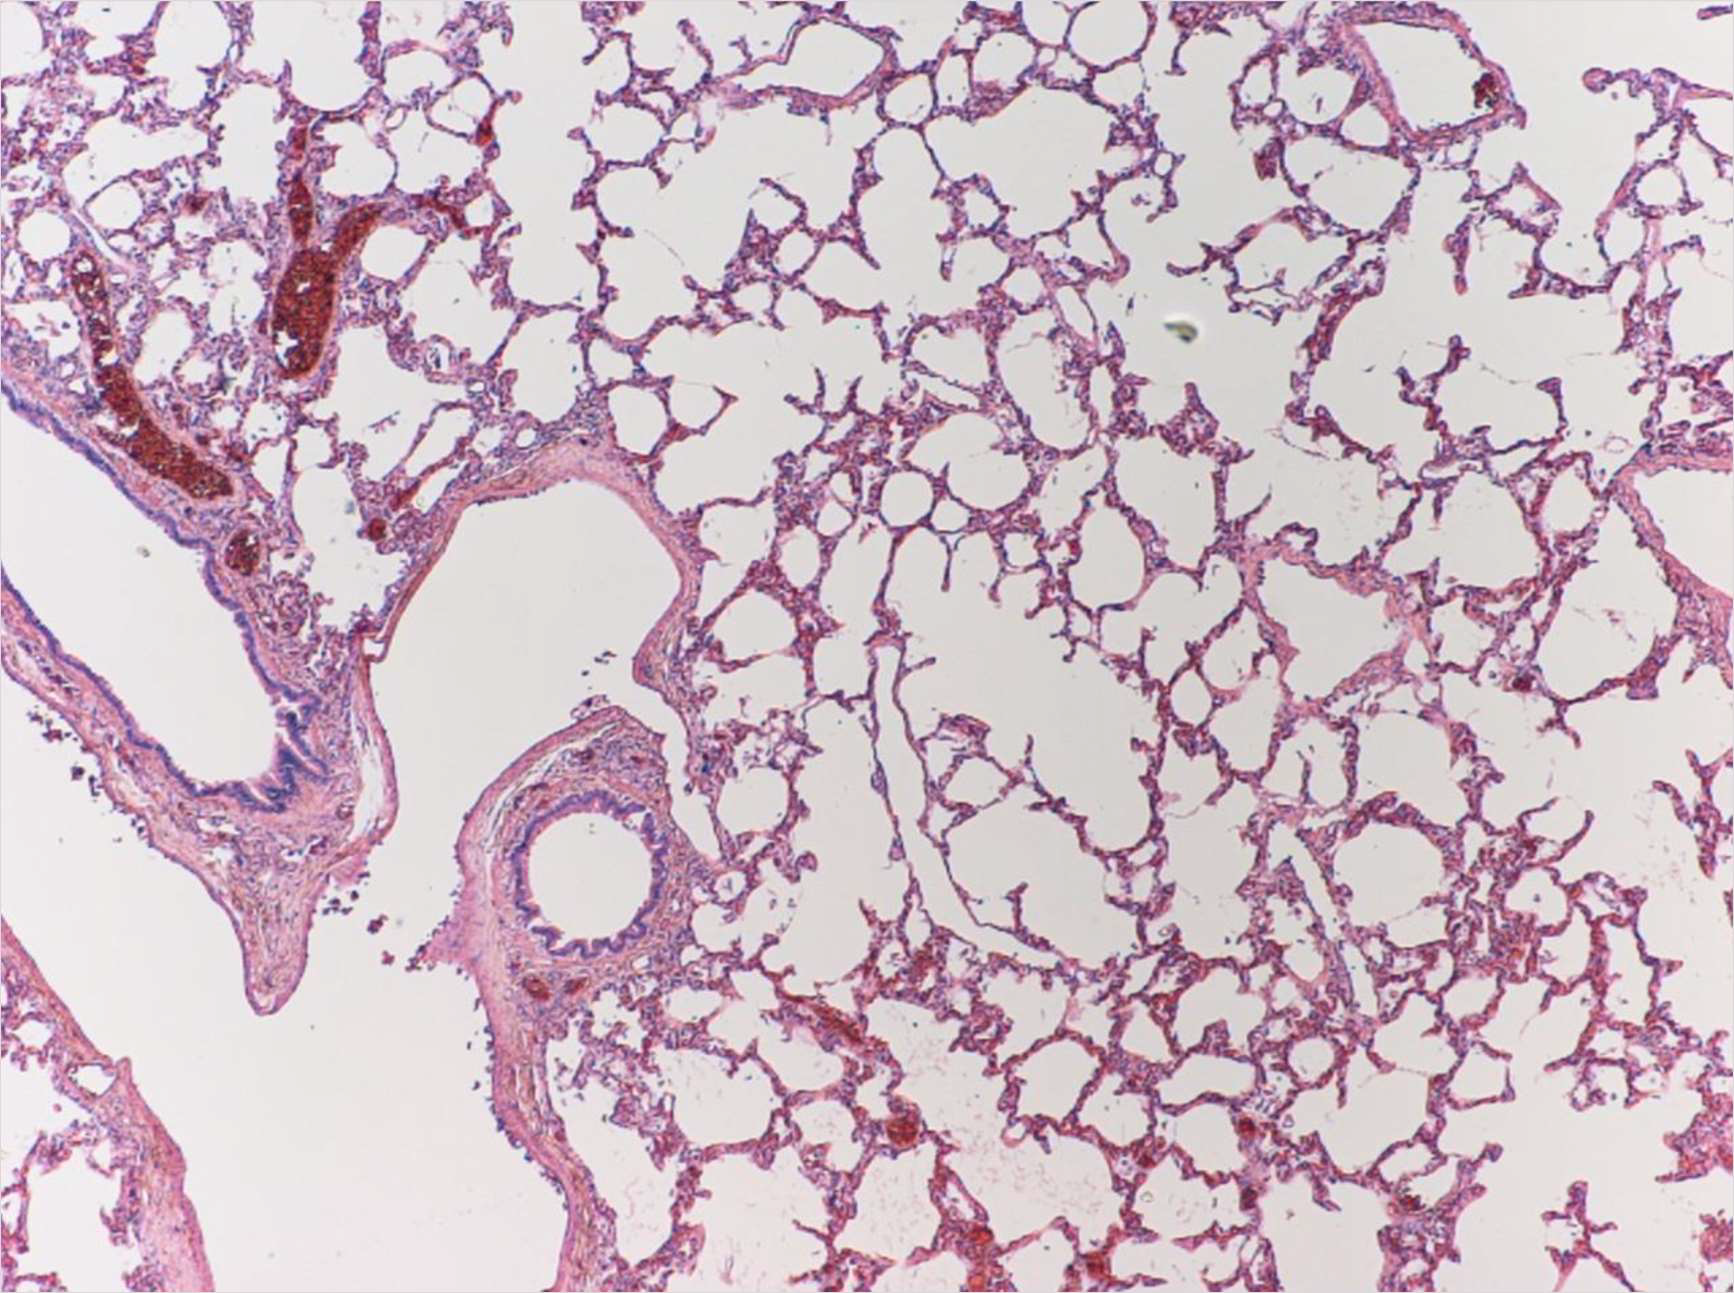

Lung

6. MedullaLung

1

2

3

4

5

6

71. Bronchiole,

2. Vein,

3. Alveolar wall,

4. Capillary,

6. Smooth muscle,

7. Blood vessel,

8. AlveoliKidney